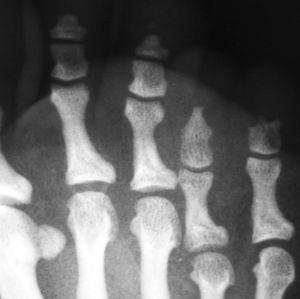

ACROOSTEÓLISIS EN PACIENTE CON PICNODISOSTOSIS

ETXEBARRIA FORONDA

Rev Esp Enferm Metab Oseas 2008;17:51

Acceso a texto completo